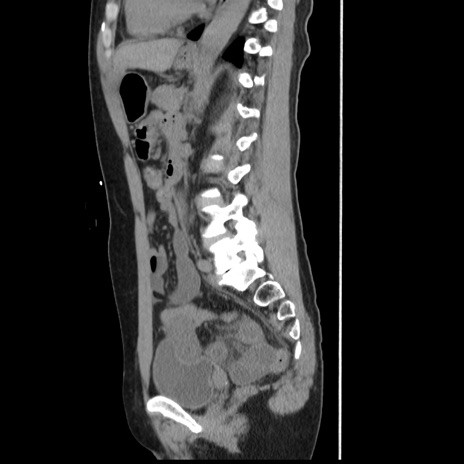

症例10(矢状断像)

【症例】 50歳代女性

【主訴】 腹痛

【現病歴】前日生レバーを食べた。今朝に排便あり。 昼前に突然発症の腹痛を生じ、当院救急外来を受診した。

【既往歴】 子宮筋腫にてで子宮全摘後

【身体所見】 意識清明、腹部:平坦、軟、下腹部やや左を中心に圧痛・反跳痛あり、筋性防御あり

【データ】WBC 7800、CRP 0.07